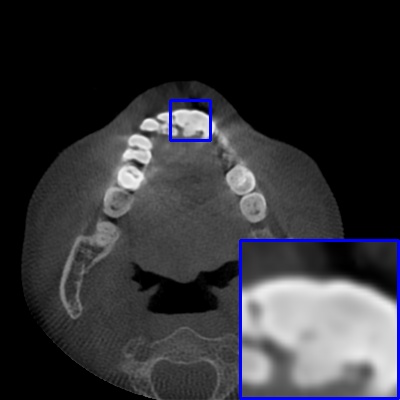

Figure 3: Visual comparison of MAR images by different methods on synthetic MA image. The PSNR (dB)/SSIM results are reported below each image for reference.

Results on synthetic MAR. In Table 1, we provide the quantitative results. One can see that our MARformer-L outperforms the other methods in terms of PSNR and SSIM, but needs only 11.76M parameters and 60.25G FLOPs. Note that the second best method Uformer-B has 50.42M parameters and 205.82G FLOPs. Besides, our MARformer-T achieves similar PSNR and SSIM results with Uformer-T, but needs only 0.40M parameters and 12.82G FLOPs compared to 5.24M and 25.39G for Uformer-T. Our MARformers also achieves faster inference speeds than the Uformers, though with inferior Dice scores, respectively. The qualitative results of visual quality are presented in Fig. 3. We observe that our MARformer-L well recovers the teeth shapes and obtains higher PSNR and SSIM results than the other comparison methods. The light-weight MARformer-L achieves similar results to Uformer-T. All these results validate that our MARformer is more efficient than the comparison methods on dental CBCT MAR.